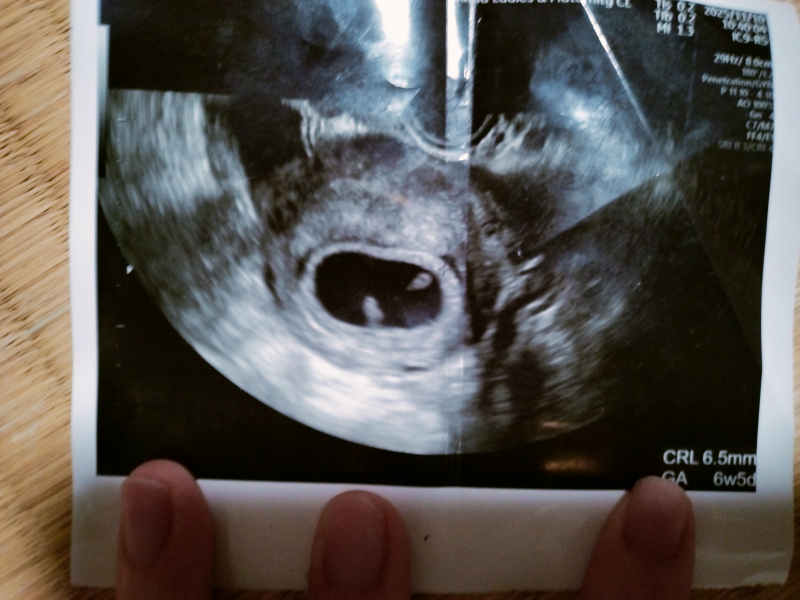

妊娠6週と4日目のエコー写真に、白くて丸い粒のようなものが離れて写っていて、心拍は取れず、CRLは6.5mmでしたが、胎嚢の大きさは分かってません。

この2つの粒は卵黄嚢と胎芽でしょうか?もし2つの粒が卵黄嚢と胎芽だった場合、こんなに離れていても心拍が取れる可能性はあるでしょうか?週数にしては胎芽が小さくて心配です

お写真を拝見しますと、おっしゃるように、子宮内に白いものが2つみえますね。

実際に拝見していませんので、なかなかはっきりとしたことは明言できませんが、確かに卵黄嚢は、妊娠5~6週頃になると赤ちゃんの姿(胎芽)と一緒に確認できることがあります。卵黄嚢が見えるのであれば、子宮内で正常妊娠しているといえます。

掲載していただいたお写真のエコーの白い部分が、卵黄嚢と胎芽かどうかは、なかなかお写真からですと明言できませんが、医師から特に何も異常の指摘がなかったということであれば、あまりご心配なさらなくてもいいように思いますよ。もしご心配であれば、また健診の際にご確認なさってくださいね。